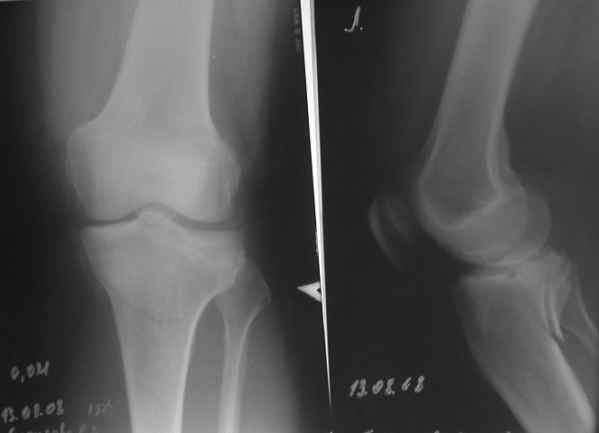

конечно есть, просто не дошли. Посылаю

Действительно, доступ капризный. Из имплантов я бы выбрал Tomofix от синтез.